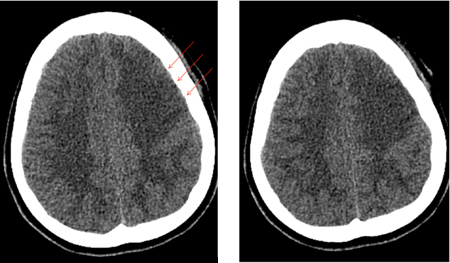

Vasospasm develops between days 4 and 14 after SAH and is seen on angiography in 50% to 70% of cases. Half of these patients develop delayed cerebral ischemia (DCI) secondary to reduced regional or overall cerebral blood flow (CBF).[190] If untreated, DCI progresses to permanent cerebral infarction in 50% of cases. Ischemic deficits may also be seen in the absence of discrete angiographic vasospasm. This is believed to be due, in part, to altered autoregulation of distal cerebral vessels, microthrombi in such vessels, and/or cortical spreading depolarization.[191] Risk factors for DCI are a poor clinical condition on admission, quantity and duration of exposure to subarachnoid blood, thick blood collections in cisterns and fissures, intraventricular blood, and duration of unconsciousness.[172][177][192][193][194][195] Although the presence of blood in the subarachnoid space is necessary to the development of vasospasm, surgical clipping, during which most of the subarachnoid blood is washed out, does not seem to carry a lesser risk of vasospasm than endovascular coiling.[196][197][Figure caption and citation for the preceding image starts]: Severe vasospasm of distal left internal carotid artery and proximal middle and anterior cerebral arteries before (A) and after (B) intra-arterial infusion of nicardipine and transluminal balloon angioplastyCourtesy of Dr Salah Keyrouz; used with permission [Citation ends].Severe vasospasm of distal left internal carotid artery and proximal middle and anterior cerebral arteries before (A) and after (B) intra-arterial infusion of nicardipine and transluminal balloon angioplasty[Figure caption and citation for the preceding image starts]: Left frontal infarct (arrows) in a patient with subarachnoid hemorrhage-related vasospasmCourtesy of Dr Salah Keyrouz; used with permission [Citation ends].Left frontal infarct (arrows) in a patient with subarachnoid hemorrhage-related vasospasm